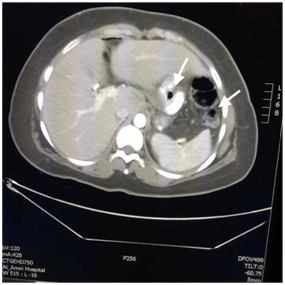

A 25-year-old woman presented with a history of controlled hypothyroidism, Laparoscopic Sleeve Gastrostomy (LSG) in 2012, and a combined Roux-en-Y gastric bypass and cholecystectomy in 2015. She presented to one of our regional hospital surgical facilities in 2016 with a 1-day history of diffuse, non-radiating, constant, and colicky abdominal pain associated with anorexia and constipation. On examination, she was vitally stable, her abdomen was grossly distended and severely tender with evidence of guarding, and her bowel sounds were absent on auscultation. Subsequently, a Computed Tomography (CT) scan of the abdomen was done, revealing a hiatal hernia of the bypassed stomach pouch with evidence of dilated jejunal and proximal ileal loops reaching 5 cm in diameter (Figure 1), and free extraluminal air locules were seen in the right side of the upper abdomen and perihepatic region (Figure 2), along with mild free intra-abdominal free fluid and diffuse fat stranding (Figure 3). She was admitted as a case of acute abdomen and small bowel obstruction secondary to bowel perforation; she was immediately booked for diagnostic laparoscopy.

Figure 2 CT scan showing a coronal section of the upper abdomen showing free air locules (arrows) representing pneumoperitoneum at perihepatic region.